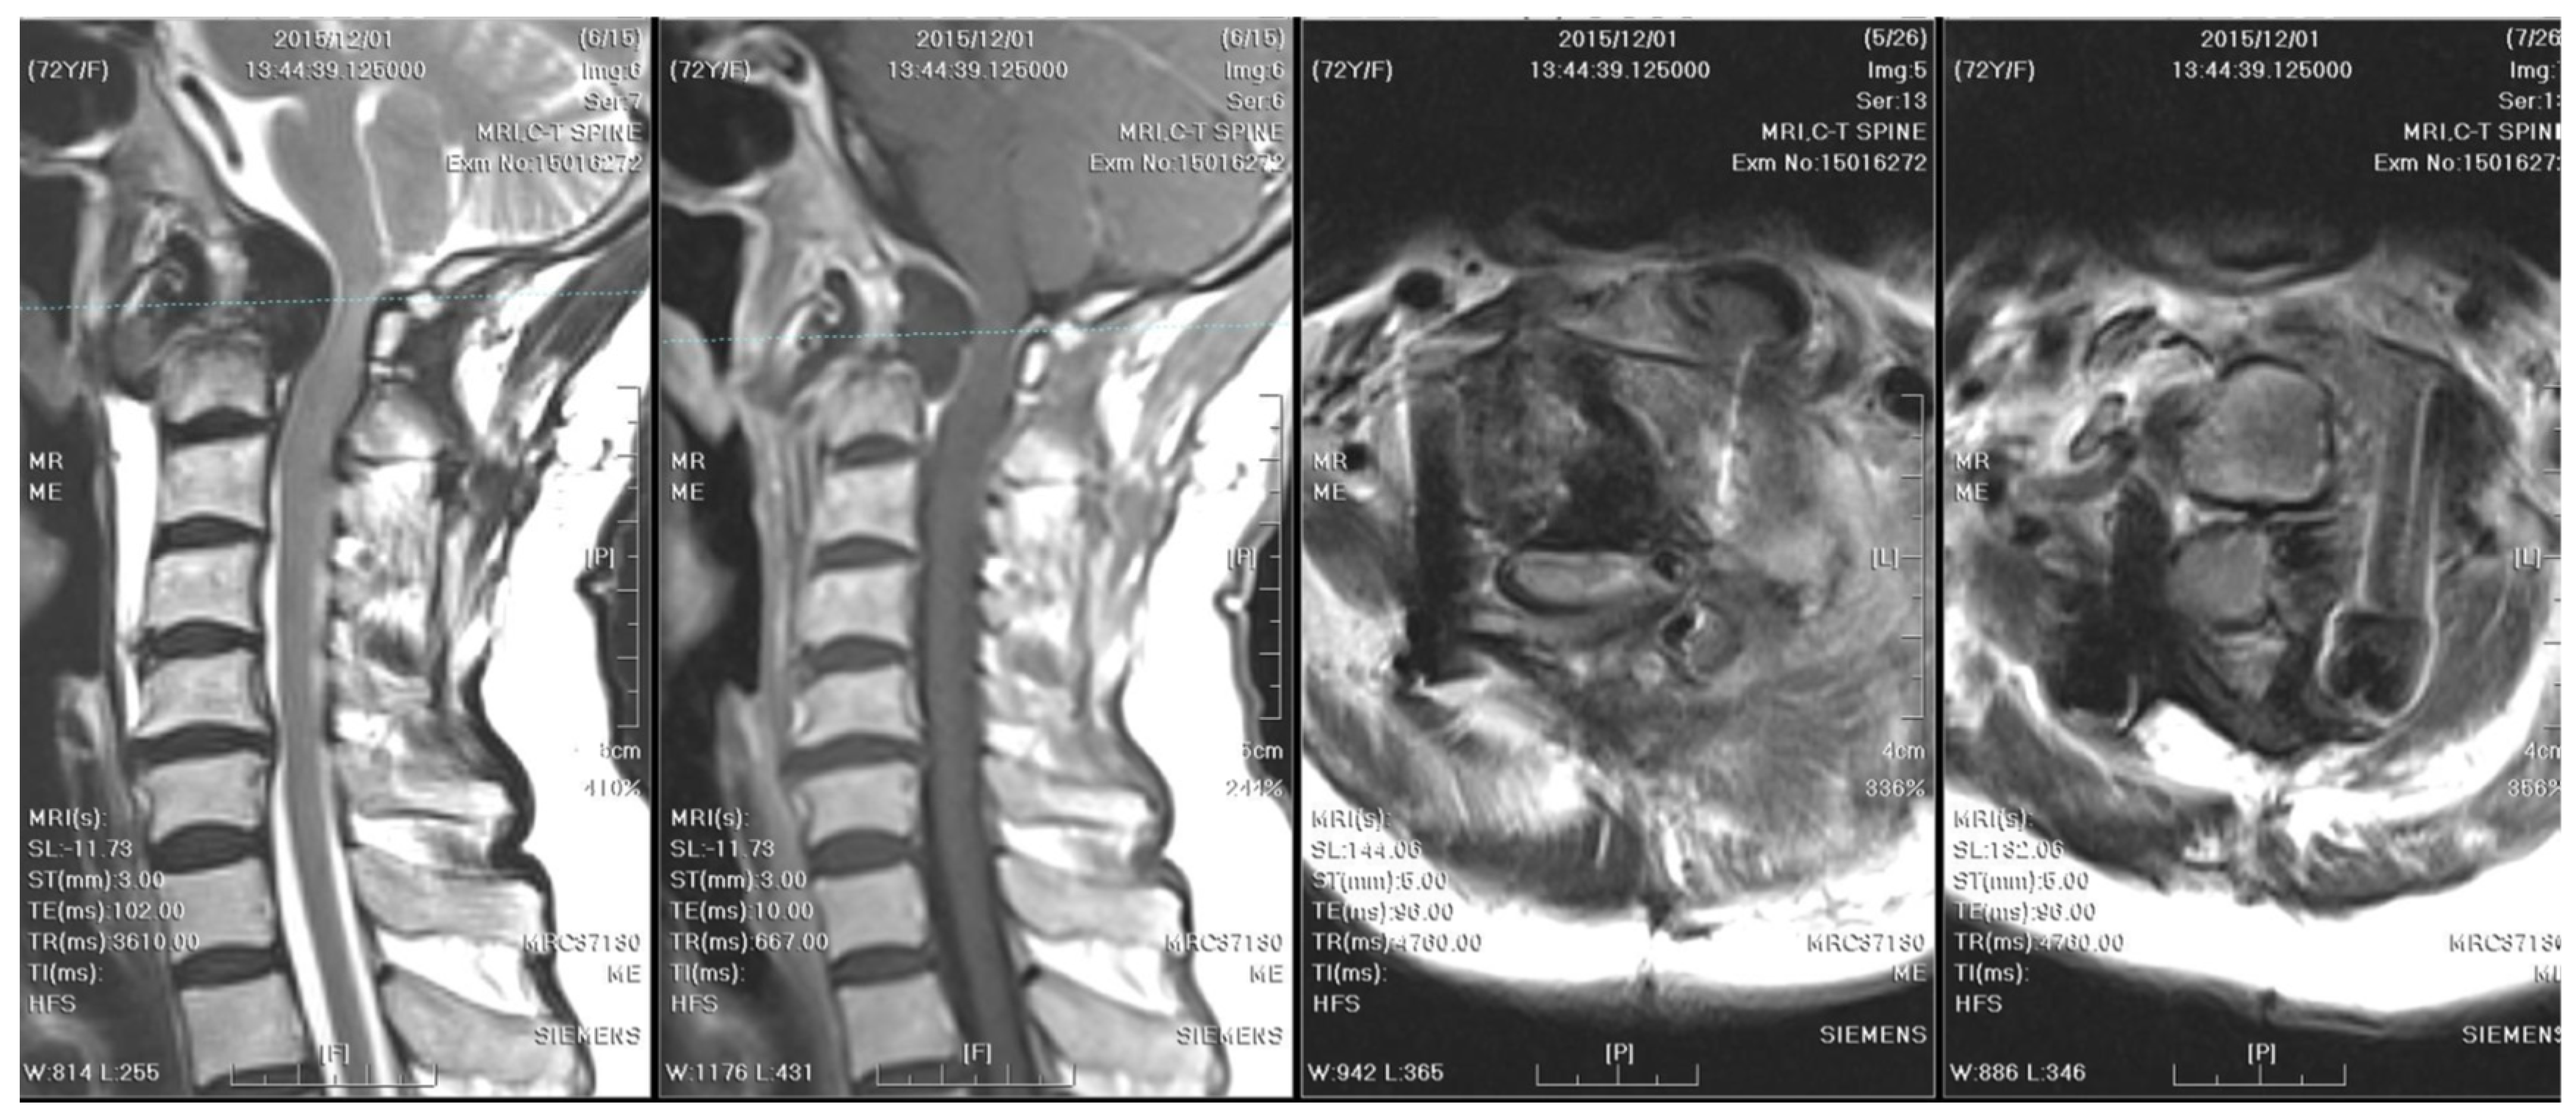

Two years after surgery, the patient experienced progressive weakness in the left upper limb and numbness in both upper limbs, which dramatically worsened within a week. A follow-up cervical spine MRI with contrast showed right rotatory C1–C2 subluxation with bony destruction and surrounding soft tissue enhancement at the atlanto-odontoid joint, leading to severe spinal cord compression with focal myelomalacia (Figure 5). The atlantoaxial abscess progressed and led to myelopathy.

Distinctive MRI characteristics help differentiate between tuberculous and pyogenic spondylitis. Tuberculous abscesses typically exhibit a thin and smooth wall, while thick, irregular, and ill-defined walls are associated with pyogenic infections [16]. TB often results in heterogeneous contrast patterns of vertebral body enhancement and bony destruction exceeding 50%, compared to pyogenic infections. On the other hand, the fragmentary or osteolytic pattern of bone lesions on CT images was a predictor for spinal TB, with an odds ratio of 3.3 [17]. Furthermore, the combination of the above CT finding and three MRI features (thin abscess wall, destruction of more than half of the vertebral body, and subligamentous spread) had an even higher diagnostic value (odds ratio of 15.58) [17]. The first cervical spine MRI and CT of our case revealed severe bony destruction (but less than 50%), heterogeneous contrast enhancement of the vertebral body, and subligamentous spread in the prevertebral area. The wall of the abscess was ill-defined, smooth, and regular. However, the thickness of the wall was equivocal (Figure 2). A cervical spine MRI performed due to progressive weakness two years later revealed a thinner abscess wall, as well as a heterogeneously enhanced vertebral body and subligamentous spread (Figure 5). From the above, although the literature has generalized several radiological traits for diagnosing spinal TB, imaging findings can still be inconclusive.

Figure 5. MRI of the cervical spine checked two years after the initial surgery demonstrates right rotatory atlantoaxial subluxation with bony destruction and surrounding soft tissue enhancement at the atlanto-odontoid joint, leading to severe spinal cord compression with focal myelomalacia. A thinner abscess wall (compared to the cervical spine MRI from two years ago), heterogeneously enhanced vertebral body, and subligamentous spread were observed.